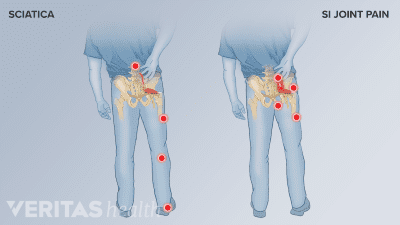

Sacroiliitis and sciatica may have similar symptoms, but their causes and treatments are different. Find out which one is causing your pain and how to treat it.